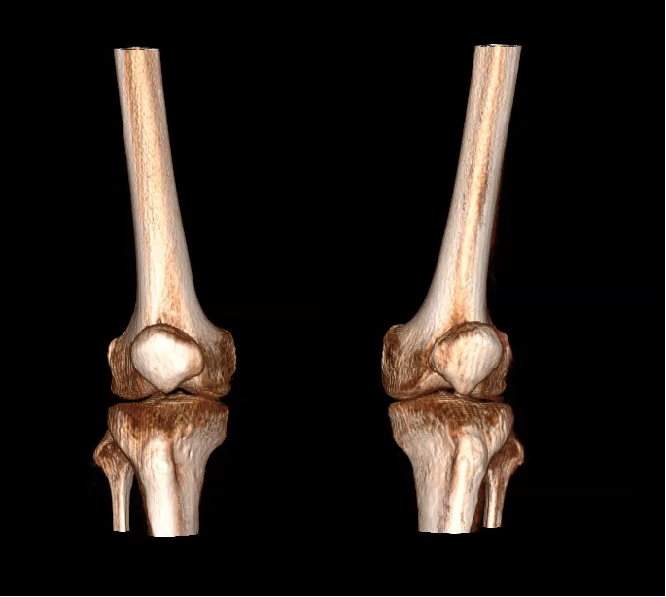

对于安健科技“WR-3D负重位动态三维影像重建系统”技术的问世,主要解决了两大核心问题:1、解决了普放DR漏诊率高的现状,常规DR设备仅有某一角度的二维影像、密度信息极差,而WR-3D能获得更丰富的诊断信息,多角度拍摄三维重建影像,任意角度任意切面以及高敏感的密度信息;2、解决了CT无法获得立位(负重位)的三维影像,WR-3D无论是在断层图像重建、MPR多平面重建、VR体绘制都有着优异的表现,而对于临床诊断尤其是骨科,负重位的影像更具有临床价值。患者在负重位状态下肌肉状态、关节间隙及骨骼力线等都与患者平躺时是明显不同的。因此WR-3D在术前精准规划与术后精准评估方面有其非常重要的临床价值。

(VR体绘制图像)